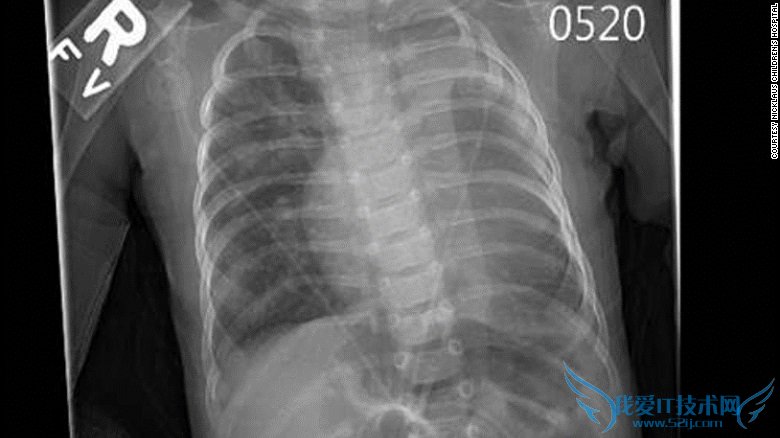

小迪根去年8月时才出生,她的心脏和肺都存在缺陷,医生之前还没见过这样的病例。她只有一个肺,几乎没有左心室。

迪根出生时只有一个肺的一半的心脏

明尼苏达州的医生说没有办法救迪根,他们让孩子回家等死